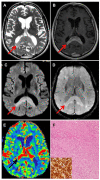

Brain biopsy is the gold standard in order to establish the diagnosis of unresectable brain tumors. Few studies have investigated the long-term outcomes of biopsy patients. The aim of this single-institution-based study was to assess the concordance between radiological and histopathological diagnoses, and the long-term patient outcome. Ninety-three patients who underwent brain biopsy in the last 5 years were analyzed. We included patients treated with stereotactically guided needle, open, and neuroendoscopic biopsies. Most patients (86%) received needle biopsy. Gliomas and primary brain lymphomas comprised 88.2% of cases. The diagnostic yield was 95.7%. Serious complication and death rates were 3.2% and 2.1%, respectively. The concordance rate between radiological and histological diagnoses was 93%. Notably, the positive predictive value of radiological diagnosis of lymphoma was 100%. Biopsy allowed specific treatment in 72% of cases. Disease-related neurological worsening was the main reason that precluded adjuvant treatment. Adjuvant treatment, in turn, was the strongest prognostic factor, since the median overall survival was 11 months with vs. 2 months without treatment (p = 0.0002). Finally, advanced molecular evaluations can be obtained on glioma biopsy specimens to provide integrated diagnoses and individually tailored treatments. We conclude that, despite the huge advances in imaging techniques, biopsy is required when an adjuvant treatment is recommended, particularly in gliomas.